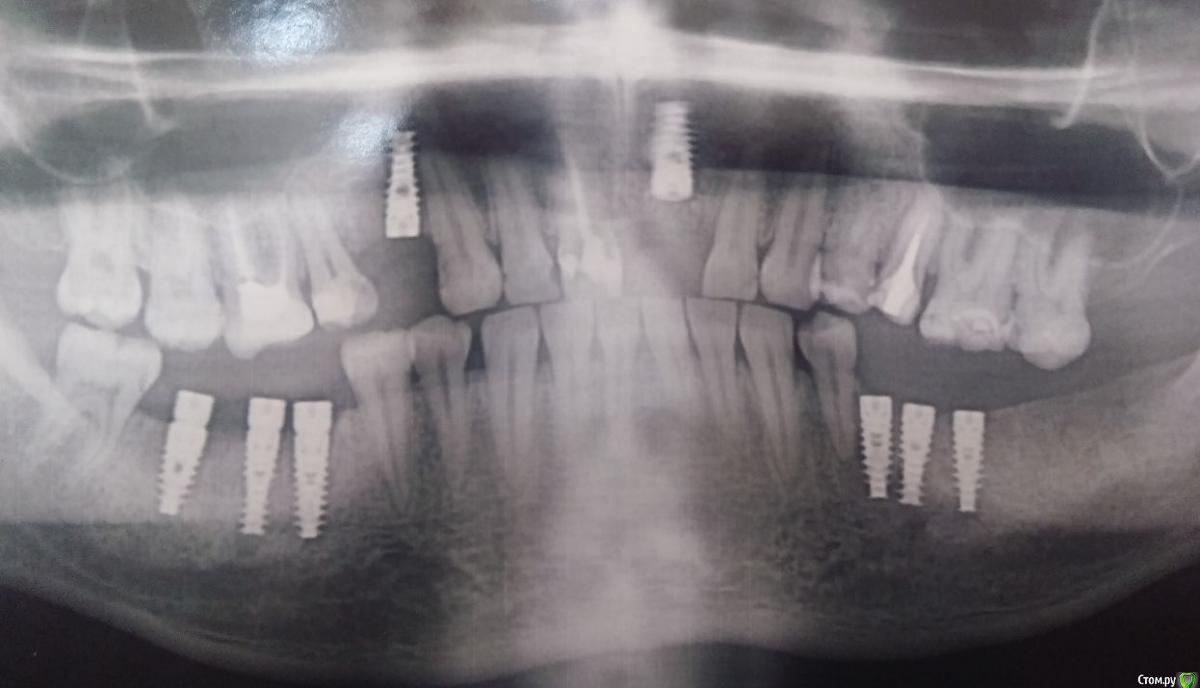

alezx Опубликовано 20 ноября, 2015 Поделиться Опубликовано 20 ноября, 2015 Всем доброго дня. Достаточно давно мне удалили 5 зубов. 9 ноября мне удалили ещё 4 зуба и поставили 8 имплантатов (альфа-био). Удаление и имплантирование прошло одномоментно. К сожалению, я ещё не делал снимок или КТ после имплантации, поэтому схематично могу показать что и где менялось на старых снимках + приложу фото там, где имплантаты видны.Комментарии к снимку:1. Удален зуб, установлен имплантат2. Удалены 2 зуба, установлены 3 имплантат с формирователями3. Удален зуб, установлен имптантат4. Установлены 3 имплантата без формирователя Все обычные последствия прошли достаточно быстро. Отек сошел к концу недели (через 5-6 дней). Болей как таковых не было, кроме первых дней и все казалось бы шло, как по маслу. Но примерно с 15 числа появилась глубокая (не знаю как верно это назвать, то есть она была не сильной и как будто где-то в глубине кости) боль с правой стороны нижней челюсти. Решив, что это просто часть последствий после тяжелой операции принял кетанов и постарался не обращать внимание. На следующий день все повторилось, к вечеру боль вернулась. И так начало повторяться каждый день.Вчера, 19 числа, я снимал швы (у другого врача) и решил проконсультироваться по поводу боли. Мне озвучили, что это вполне нормально и должно скоро пройти.Вечером кетанов решил, что хватит с меня и действовать перестал. Боль уже добралась звоном до уха. Ночь прошла интересно. В 5 утра я выпил нимесил и тогда смог уснуть. В это время боль уже отдавала в крайних нижних зубах при надавливании на них + немного побаливало с левой стороны челюсти (там уже все заросло десной и до этого времени не беспокоило). Разумеется судьба привела меня сюда и судя по прочитанному из других тем, боль на 10 день после операции - это совсем не нормально (успокойте меня, если ошибаюсь).Мысли тревожат вариантами "не прижились имплантаты" или "задет нерв", хотя второе сомнительно, ведь у меня не было онемения.. Хотелось бы услышать ваши мысли по поводу происходящего со мной. Так же уточню:1. Снимок сделаю, вопрос только в его срочности (бежать прямо сейчас с работы или можно подождать начала следующей недели?)2. К сожалению, наблюдаться дальше у того же хирурга, что делал операцию я не могу. Планировал протезироваться в одной из клиник города, но ещё не выбрал в какой. Вариант обращаться даже за переделкой сделаного в то же учреждение - крайний для меня.3. О состоянии 8-рки в курсе, стоматологию планировал после этой операции. (Опять же, на форуме прочел, что пишут об обратном (лечение-удаление-имплантация), но на момент косультации со стоматлогом было озвучено "Удаляй все, потом приходи". Только вот не знаю, приходить ли к нему...) Ссылка на комментарий

alezx Опубликовано 25 ноября, 2015 Автор Поделиться Опубликовано 25 ноября, 2015 Сделал снимок. Надеюсь качество удобоваримое. Про боли - продолжаются, ближе к вечеру. Не регулярно. За все дни только вчера не выдержал и принял кетанов, до этого было терпимо, хоть и дискомфортно. Есть мысль о том, что это из-за еды. Может быть зря я перешел на относительно твердую пищу (картофельное пюре, супы с овощами) и нужно было продолжать детское питание и йогурты из трубочки? Десна все ещё не зажила со стороны, где имплантаты с формирователями, между ними небольшая бороздка (попадание горячего-холодного-любого в неё могло спровоцировать?) Ссылка на комментарий